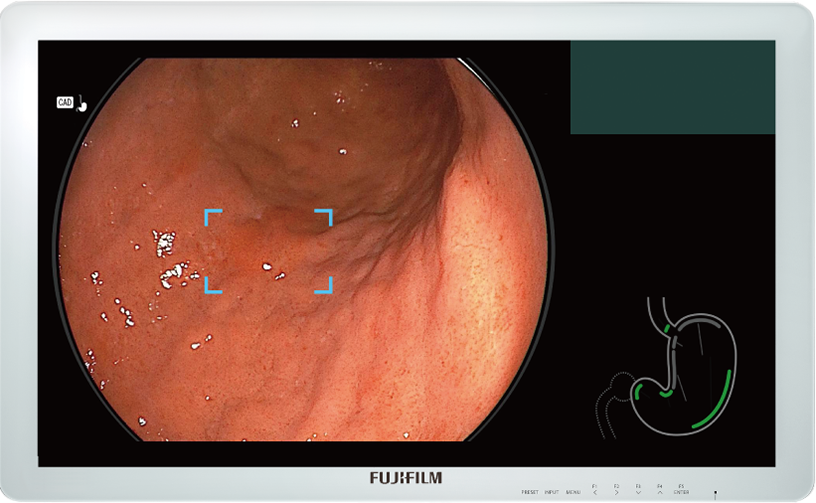

Detects the area that may be gastric neoplastic lesion and displays it on the main monitor in real-time.

Detection Box

Indicates the area where this software suspects that a lesion is present.

When a still image is captured, Landmark Photo Checker is activated to check if the major landmarks in the stomach are properly captured.

- Oesophagogastric junction

- Cardia (near field view)

- Cardia and fundus

- Body, lesser curvature (retroflex view)

- Pylorus (near field view)

- Body, greater curvature (forward view)

- Angulus

Before examination (Left) Complete state (Right)

Graphical user interface of CAD EYE is integrated and displayed together with an endoscopic image on a single monitor. It does not interfere with clinical images and minimizes required eye movement.